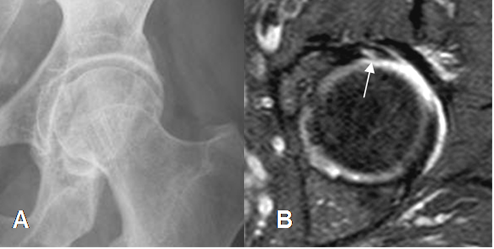

Fig 115. Quiste paralabral.

A: Rx AP. Prominencia del borde lateral de la cebaza femoral, por pinzamiento tipo cam.

B: RM coronal en T2 y C: RM coronal en STIR. Imagen quística e hiperintensa en ambas secuencias, hacia la región superoexterna del reborde acetabular, que corresponde a quiste paralabral.